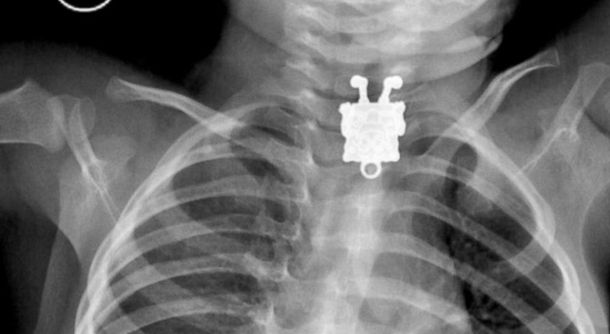

"Yo pensé que era sólo un alfiler, pero cuando vi la radiografìa frontal me encontré a Bob Esponja que me miraba con una sonrisa", explicó el doctor Ghofran Ageely a la cadena de noticias ABC.com sobre las radiografías que fueron publicadas en el sitio LiveScience.

"Me quedé impresionado [con la radiografía] porque pudimos verle las pecas, los zapatos y los dedos [a Bob Esponja]. ¡Increíble!", expresó el médico.

Al aprecer, el niño se había tragado un pendiente de su hermana y el dije había quedado atrapado en su esófago. Por fortuna los médicos lograron extraerlo sin mayores complicaciones.